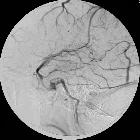

• Lateral superfical veins of the brain - Ganzer Fall bei Radiopaedia

middle cerebral vein • Superficial middle cerebral vein of Sylvius (DSA) - Ganzer Fall bei Radiopaedia

The superficial middle cerebral vein (SMCV), also known as the Sylvian vein, is one of the superficial cerebral veins. It usually courses along the Sylvian fissure posteroanteriorly and drains numerous small tributaries from the opercular areas around the lateral sulcus. It curves anteriorly around the tip of the temporal lobe and drains into the sphenoparietal sinus or directly into the cavernous sinus. There is however, significant variation (see below).